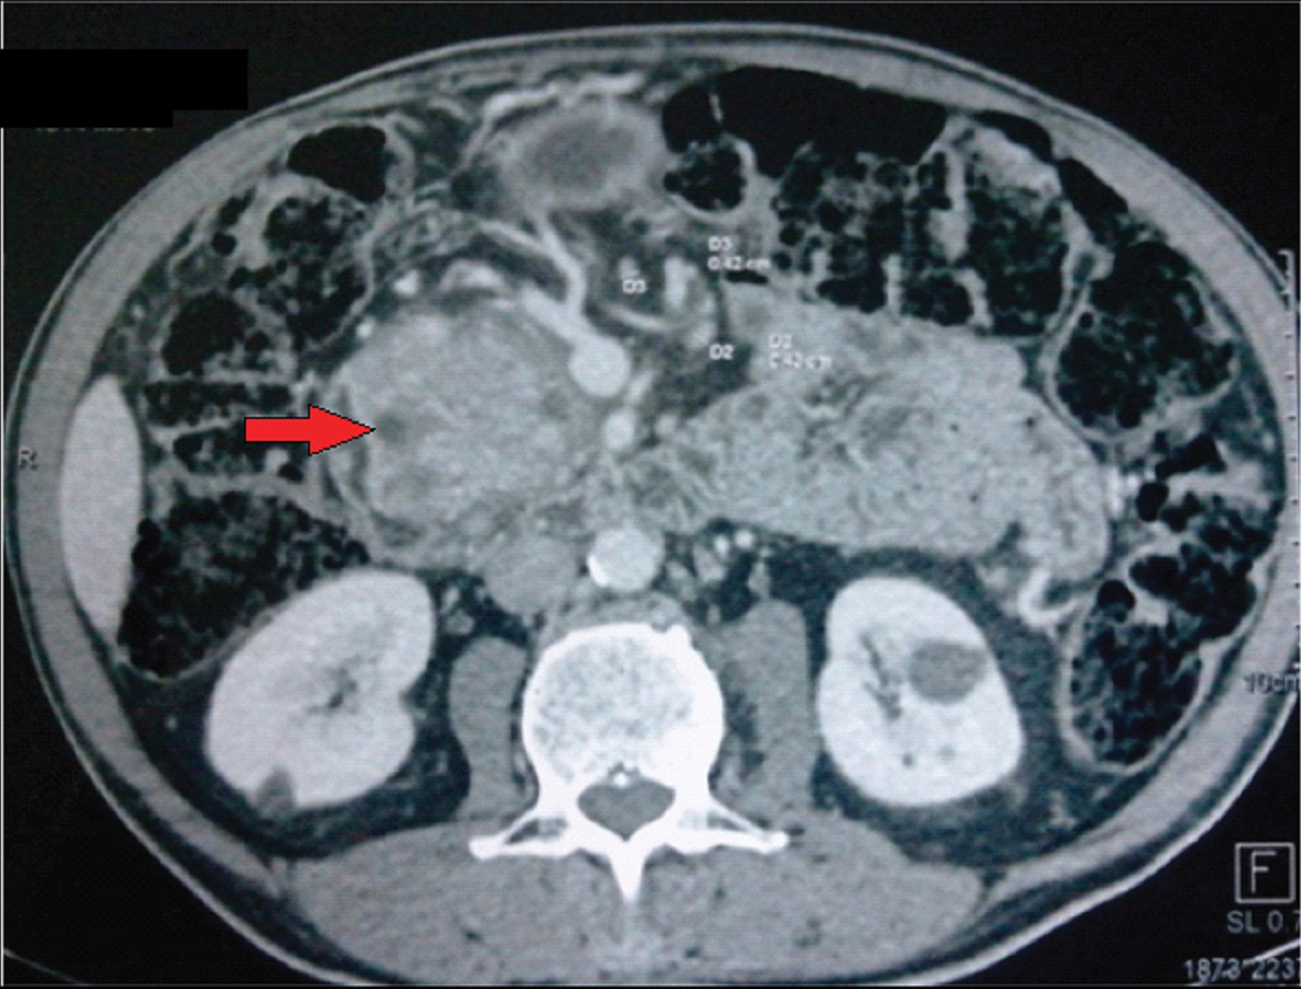

He was readmitted six months later with jaundice. CT scan [Table/Fig-1] was remarkable for a major dilation of the Wirsung duct associated to an enlargement of the main bile duct. MRCP [Table/Fig-2] showed enlargement of the pancreatic gland, multiple cystic lesions of the head of the pancreas with a major dilation of the main pancreatic duct. Intraductal hyperintense lesions were seen in the head, body and tail of the pancreas in the diffusion weighted images. There were no signs of liver or lung metastases. Endoscopic ultrasound with consideration for aspiration of cyst fluid was not done for logistical reasons. Lateral vision duodenoscopy failed to find mucinous output through the papilla. Carcinogenic embryonic antigen level was 5 UI/l. He was subsequently diagnosed with multifocal ITPN and underwent total pancreatectomy and splenectomy [Table/Fig-3].

Abdominal CT revealing enlargement of the pancreatic gland, dilatation of the main pancreatic duct and with multiple cystic lesions of the head (red arrow).